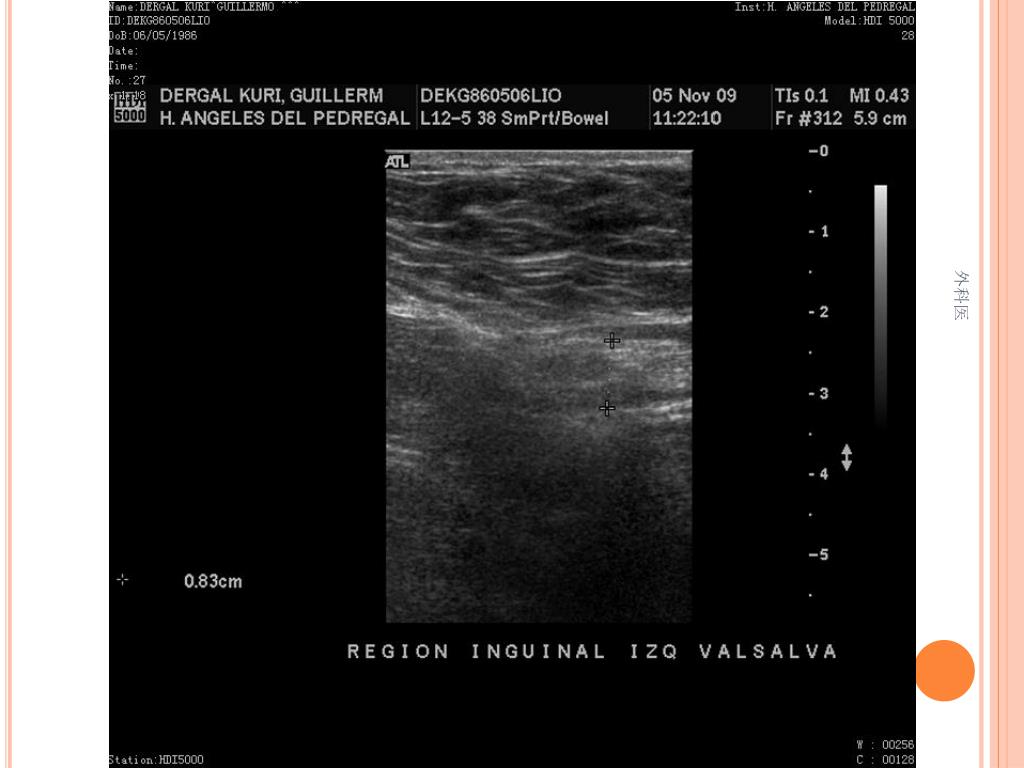

44. Tips • Leucocitos Mas de 20000/ml • Mas de 20% de la apéndices no se llenan con el bario por enema. • USG sensibilidad del 85% y Especificidad de mas 90% para Apendicitis Aguda. • TAC de Abdomen cortes de 5mm, sensibilidad y especificidad del 90% para dolor abdominal. • Analisis de 75000, taza de apendice negativa de 6% Hombres y 13% Mujeres 外科医